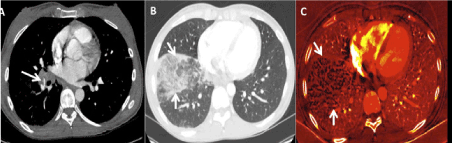

There are many pectoral imaging protocols which are able to profit DECT. let's say, iodine improvement maps offer physiological information regarding the introduction of iodine at intervals the internal organ parenchyma, which may be helpful in identification introduction deficits because of respiratory organ emboli or various conditions like emphysema [24]. Initial studies counsel that quantification of the degree of iodine improvement might even be helpful in differentiating between benign and malignant internal organ nodules [15]. DECT has to boot been useful for patients are unable to spice up their arms on top of heads as a result of post method of DECT pictures can limit artifacts because of beam hardening caused by the arms. Similarly, streak artifacts because of metal prostheses in, let's say, the shoulder or the spine, are usually reduced with DECT. Moreover, as a result of iodine improvement is larger at lower Kev, a lower dose of iodine medium is usually used once imaging with DECT (Figure 7) if medically indicated [15,25,26].

Figure 7. Patient with one urinary organ and shortness of breath had scattered respiratory disease and pathology on chest pictures. The patient underwent a DECT embolism protocol CT with solely twenty-five ccs of contrast material (generally 80-100 cc of contrast material is used). customary CT pictures at sixty Kev (a and b) improvement distinction improvement in pneumonic arteries (main, lobar, segmental, and subsegmental). pneumonic blood volume image (C) shows scattered defects (arrows) in line with areas of pulmonary emphysema (these defects would have reduced the sensitivity and specificity of nuclear V:Q scan).

CT angiography of the pneumonic arteries (CTPA) could also be a sensitive and speedy methodology for detecting emboli at intervals the pneumonic arteries. it's replaced typical scintigraphy methods for ventilation/ perfusion imaging in AN passing majority of patients. optimum single-energy CTPA desires shut attention to the temporal order of image acquisition once the excellence has been administered. Inappropriate temporal order of acquisition of the image may result in a non-diagnostic examination, that's means less common with DECT than with single energy CTPA. to boot, distinction improvement in smaller branches of the pneumonic arteries is sometimes higher on DECT than on single-energy CTPA. Post method of DECT pneumonic roentgenography can generate virtual non-contrast pictures, customary CPTA pictures, and iodine distribution map that will show if their square measure any perfusion deficits. Deficits caused by embolism square measure typically wedge-shaped. Thus, DECT has the potential to increase the accuracy of identification for pneumonic emboli. to boot, the size of the perfusion deficit is prognostic as larger perfusion deficits square measure involving poorer prognosis [15,26,27].

Chest CT examinations are performed for form of reasons, alongside staging of cancer, assessing response to treatment, characterization of abnormalities, and for symptomatic patients with traditional photography pictures [26]. in addition to providing customary CT pictures obtained from routine chest single-energy CT, a contrast media increased routine DECT permits synchronic assessment of the pneumonic arteries and provides just about an identical information as that obtained through an embolism protocol [15]. Iodine improvement maps offer physiological information and build it easier to acknowledge pathologies like pneumonic pathology (Figure 8), respiratory illness and pathology [26]. to boot, characteristic patterns of introduction deficits are concerning different internal organ pathologies, like pulmonary emphysema and air trappings. DECT has similar blessings for cancer staging, response to medical aid and malady looking. the property, so iodine uptake, can diminish in neoplasms that area unit responding to medical aid before any shrinkage of tumor happens. in addition, DECT can differentiate between iodine improvement and calcification, which might be observed in liquid body substance nodes in non-contrast pictures and maybe a cause confusion in single-energy CT [23].

Figure 8. customary CT pictures (A and B) at sixty Kev demonstrate occlusive filling defect (arrows) among the right interlobar artery pulmonarias and consolidation at intervals the correct lower lobe. pulmonary blood volume image (C) demonstrates a neighborhood of reduced iodine uptake (arrows) that's larger than the size of consolidation. This opacity is in line with pulmonary infarction.